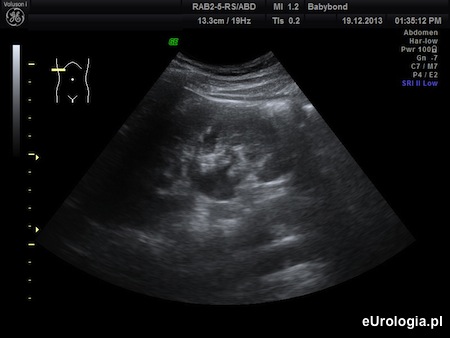

Fot. Poszerzenie układu kielichowo-miedniczkowego prawej nerki - obraz USG.

Z przedstawionego opisu wynika, że przebyła Pani atak bólu, który z opisu może odpowiadać kolce nerkowej. Z protokołu USG, który wysłała Pani na adres redakcji i załączonych zdjęć USG wynika, że układ kielichowo-miedniczkowy nerki jest umiarkowanie poszerzony co może sugerować przeszkodę w odpływie moczu z nerki. Poszerzenie UKM, krwiomocz i kolka nerkowa są objawami, które wymagają diagnostyki urologicznej. Konieczne są dodatkowe badania, które pozwolą na ustalenie przyczyny opisywanych objawów. Więcej informacji można znaleźć w artykule: Poszerzenie UKM - diagnostyka.